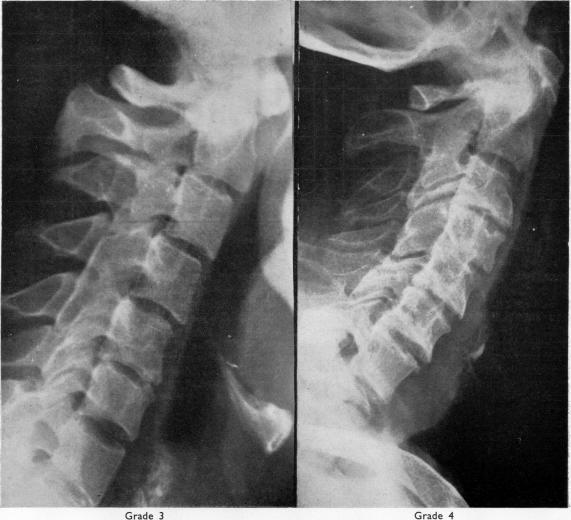

Rheumatoid arthritis of the cervical spine in the adult.

Ann Rheum Dis. 1958 Sep;17(3):303-13. doi: 10.1136/ard.17.3.303.